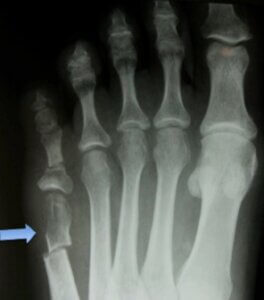

تمامی افرادی که علائم شکستگی استخوان متاتارسال پنجم را تجربه می کنند باید هر چه سریع تر جهت دریافت تشخیص و درمان مناسب به جراح ارتوپد مراجعه نمایند. جراح جهت تشخیص مناسب مشکل نحوه بروز آسیب یا زمان شروع درد را از بیمار سوال می کند. پزشک با فشار دادن آرام بر نواحی مختلف پای مبتلا را معاینه، محل درد را مشخص و انجام تصویر برداری اشعه ایکس را تجویز می کند.

از آن جایی که شکستگی جونز گاهی اوقات در تصویر برداری های اولیه مشخص نمی شود امکان دارد دیگر آزمایش های تصویر برداری نیز برای فرد تجویز شوند. شکستگی جونز معمولا در تصاویر اشعه ایکس پای آسیب دیده نمایان است. در صورت عدم مشاهده شکستگی در تصویر برداری با اشعه ایکس، تصویر برداری با امواج مغناطیسی (MRI) مفید خواهد بود. آزمایش سی تی اسکن برای سنجش التیام شکستگی ها به کار گرفته می شود.